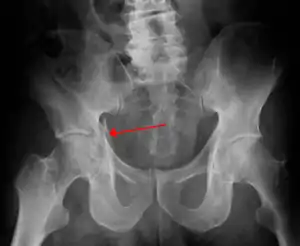

Fractures of the acetabulum occur when the head of the femur is driven into the pelvis. This injury is caused by a blow to either the side or front of the knee and often occurs as a dashboard injury accompanied by a fracture of the femur.[1]

| Acetabular fracture as seen on plain X-ray |